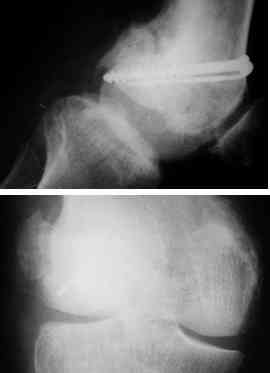

This 20 year old patient sustained a fracture in the lower end of the femur, one and a half years ago, with a compound wound over the fracture area. Notes at that time mention a compound fracture dislocation, with a loss of part of the lateral condyle. This was treated by debridement, and external fixation. After two weeks, the lateral condyle (coronal fracture) was fixed by a screw and k wire in an AP direction.

I cannot make certain from the AP whether the screw and KW are still present. The lateral however shows that the lateral condyle was fixed with disregard to the bone defect. So it was proximally displaced in relation to the medial condyle with the resultant valgus. I would do an open wedge osteotomy with bone graft and internal fixation. However, this would require a precise estimate of the correction angle and placement of the fixation device. I would use a DCS.